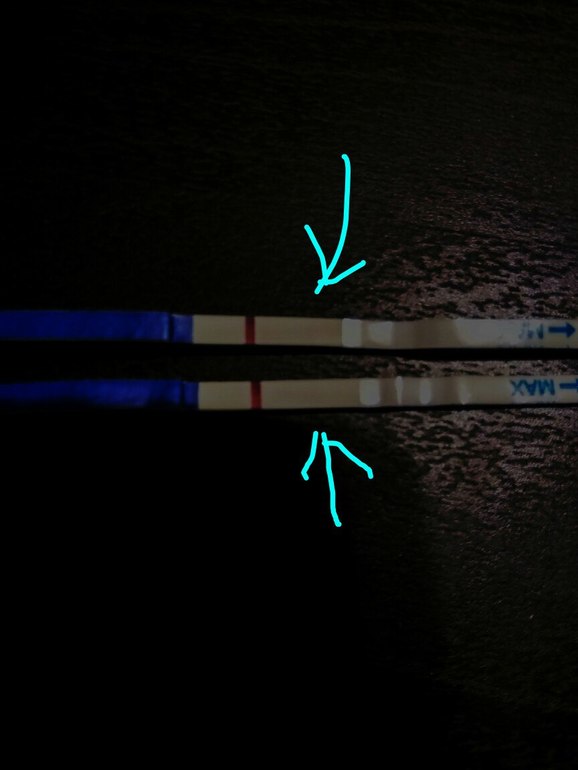

Здравствуйте девушки. Был укол Овитреля 250 (6500) 20.12. Овуляция была 21.12. Посмотрите тесты. Верхние две фотографии 28.12. (Под микроскопом что то видно...либо воображение ) нижние сегодня, 29.12. Сегодня 9 дпо.

А это сегодня

Вроде же ярче... ХГЧ вроде вышел, врач сказала, выходит через 4 дня, но может до 10 дней быть. Сегодня как раз 10 день после укола. Было 2 дф.

Полоска точно есть! Желаю чтобы это была Б!👶

Это ваша кроха привет передает.На первых тестах пусто.Такие полоски за полоски не принемаю.А вот на втором четкие //.Легкой Б!!!

на верхних не вижу ...а нижнем хорошо видно  ...не зря значит глазки ломаем